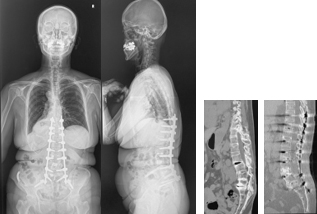

前方後方矯正固定術

せぼねが大きく変形している場合や再手術の際に前方手術と後方手術を両方行って、せぼねの矯正と固定を行います。

1日で両方の手術を行う場合と2日間に分けて手術を行う場合があります。大人の患者様では3週間程度で場合によってはリハビリテーション病院へ転院をしていただき、さらにリハビリテーションを行います。